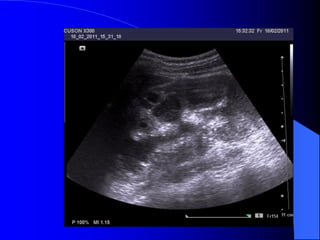

- Trãn siãu ám phaït hiãûn tháûn âa nang, ngay

caí åí giai âoaûn såïm, tháûn låïn våïi ráút nhiãöu

nang nhoí. Khi nang bë nhiãùm khuáøn hay

xuáút huyãút seî tháúy cáúu truïc ám cuía caïc nang

khäng âäöng nháút, thaình nang daìy, väi hoïa.

Siãu ám âäöng thåìi coï thãø tháúy nang åí gan

hoàûc tuûy, laïch trong häüi chæïng Von Hippel -

Lindau.